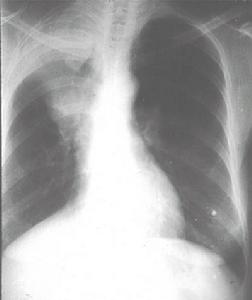

X線胸片可見雲絮狀斑片影,大小、形狀及位置都不恆定,呈遊走樣,於短期內消失及另一部位再發。偶見雙肺瀰漫顆粒狀陰影需與粟粒性肺結核鑑別。

近年來有一種"嗜酸細胞增多性哮喘病"或"暴發性哮喘性嗜酸細胞增多綜合徵",在國內若干地區暴發流行,可見於嬰幼兒、年長兒至成人。患兒不發熱或有低熱,突出表現為哮喘與乾咳,有時出現瘙癢性皮疹。病情嚴重時,偶可因支氣管、毛細支氣管梗阻及心力衰竭而危及生命。X線胸片上多數有肺紋理增加及肺氣腫,少數有片狀或網點狀陰影(圖2410)。血內嗜酸細胞增多可高達20%以上。病因未明,有些作者認為是蛔蚴在體內移行的表現,有人推測一部分流行可能與病毒感染或真菌孢子大量吸入有關。